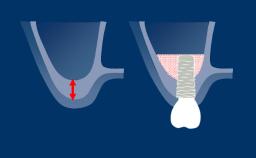

O planejamento de implante determinado por prótese garante que a instalação do implante seja compatível com o resultado final desejado, que é um fator-chave para resultados bem-sucedidos na terapia de implante. As tecnologias digitais agora disponíveis no campo da implantodontia facilitam o planejamento de implantes dirigidas por prótese dentária. Os benefícios dessas tecnologias incluem melhorias significativas na avaliação do paciente e no planejamento do tratamento, permitindo que os clínicos posicionem os implantes de suporte com um alto grau de precisão. Este Módulo de Aprendizado discutirá o uso rotineiro do planejamento baseado em computador para a instalação de implantes.